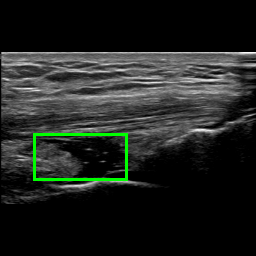

A joint recess can be distended due to three main reasons: it is filled with synovial liquid, it is filled with blood (a condition known as hemarthrosis), and its membrane is thicker due to an inflammation known as synovitis. When the SQR is distended, it appears thicker on the US image. In some cases this can be clearly visible because the joint recess appears as a large dark area. Figure 2 shows three examples of the longitudinal SQR scan. In Figure 2a the SQR is the dark area shown in the green box. In this case the SQR is thin, hence it is not distended. Vice versa, in Figure 2b the SQR is much thicker, indicating that it is distended. While Figure 2a and 2b show two characteristic examples with stark differences, there are borderline cases where the SQR appears slightly enlarged but it is not distended (see Figure 2c) or it is very slightly distended.

Refer to caption

(a) Non-distended SQR

(b) Distended SQR

(c) Borderline Non-distended SQR

Figure 2: Examples of longitudinal SQR scans